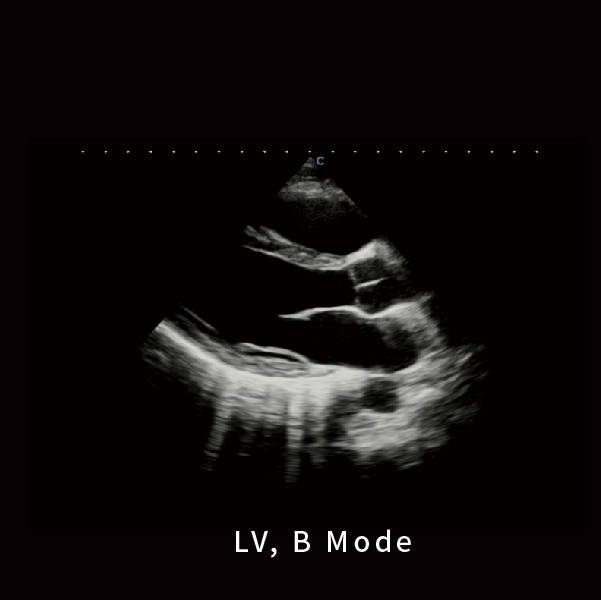

左心室,B 模式